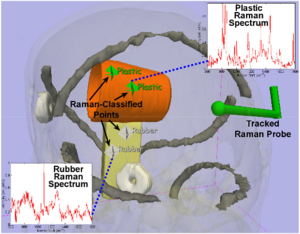

Registered, Sensor-Integrated Virtual Reality for Surgical Applications

Publication: IEEE Virtual Reality Conference 2007; PDF

Authors: Brady W. King, Luke A. Reisner, Michael D. Klein, Gregory W. Auner, Abhilash K. Pandya

Institution: Wayne State University, Detroit, Michigan, USA

Background/Purpose: The visualization for our image-guided surgery system is implemented using 3D Slicer, an open-source application for displaying medical data. 3D Slicer provides a virtual reality environment in which various imaging modalities (e.g. CT or MRI data) can be presented. The software includes the ability to display the locations of objects with respect to 3D models that are derived from segmentation of the medical imaging.

We modified 3D Slicer in several ways to adapt it to our application. First, we developed a TCP/IP interface that receives the tracking data for the MicroScribe and displays its position in the VR environment relative to the medical imaging data. This allows us to track the Raman probe in real-time. Second, we developed a way to place colored markers that indicate tissue/material classification on the medical imaging data. The combination of these modifications enables us to denote the location and classification of tissue/material scanned with the probe in near-real-time.